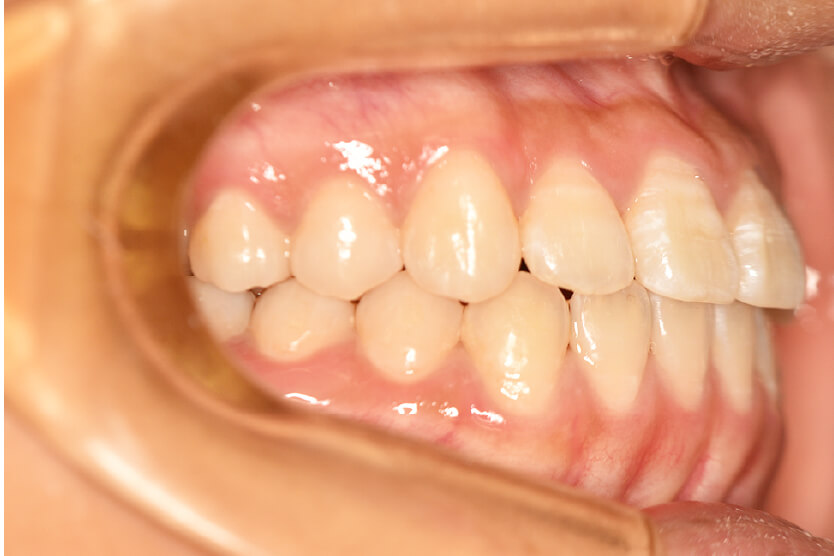

| 治療内容の詳細 | 初診時12歳の女性で、上顎前歯部の反対咬合を気にされ来院されました。 検査の結果、下顎前突、上顎前歯部叢生および上顎側切歯反対咬合を伴うアングルⅢ級不正咬合と診断しました。 治療としては、リンガルアーチを使用して、上顎側切歯を前方へ移動させ、反対咬合の改善を行い、マウスピース型矯正装置(インビザライン)で配列を行いました。 治療期間は1年5か月でした。 |